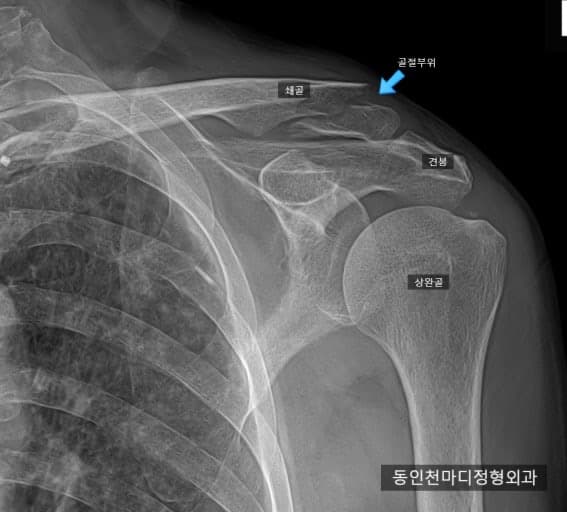

지금 4주차인데 골전이 나오지도 않았는데 의사거 팔걸이를 무작정 풀자고 하는데 풀어도 되는건가요? 지금도 윰직이면 통증있고 심지어 3주차보다 더 틀어지고 벌어졌어요 저 사진은 제 사진은 아닌데 저런식으로 뼈가 밑으로 틀어졌는데 기능상 문제가 없는게 맞는건가요? 그리고 원위부 골절에는 팔자붕대는 효능이 없다는데 팔자붕대로 바꾸고 싶은데 안되는건가요?